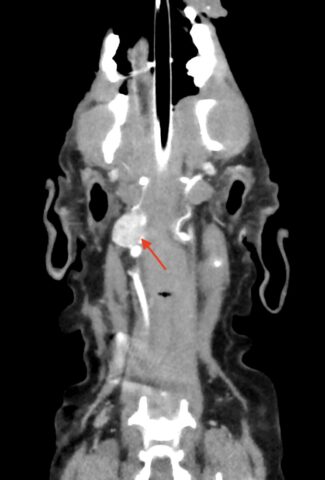

特にCT検査や細胞診検査、病理検査はより専門的な知識が必要です。

当院では、CT検査、細胞診検査、病理検査に特化した各診断医と連携を取り、検査所見を読み取ることで、より適切な診断を下させるよう努めています。

当院では約5秒で動物の全体をスキャンするCTがございます。これにより、動物への麻酔の負担を軽減して、撮影が行えます。また、動物の状態が悪い場合には麻酔をかけずに撮影を行うこともあります。撮影したデータは画像診断医“によって”正確な診断を行っております。動物のがんを早期に発見してあげることが何よりも動物に健康でいてもらえることに繋がりますので定期的な健診にも当院へお越しください。